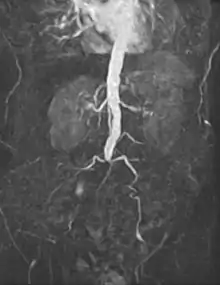

![]() Open infrarenal aortic repair model | |